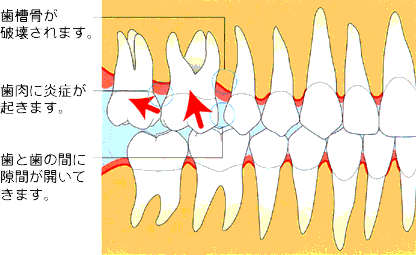

薬物性歯肉増殖症

歯肉増殖症の原因となる薬物とその発症頻度:

フェニトイン(抗痙攣薬:てんかん)約50%

ニフェジピン(血管拡張:高血圧症、狭心症)約20%

シクロスポリン(免疫抑制:臓器移植、自己免疫疾患)約30%

一般に、歯肉増殖症は薬を服用して2~3か月後から兆候が現れ、歯と歯の間の歯肉が著しく肥大化します。

重度の症例では、盛り上がった歯肉が周囲の歯を覆ってしまい、歯が隠れたり、移動することもあります。

また、もともと歯肉に炎症があると発症しやすく、放置すると炎症がさらに広がって歯周病が進行する可能性も十分に考えられます。

治療は軽度の症例では、増殖部分を清潔に保つことで歯肉肥大が改善しますので、歯科衛生士に専門的な口腔清掃指導を受け、口腔ケアを励行することが重要です。

中等度以上の歯肉増殖症では、歯肉を切除する手術を行います。

術後の注意点は、薬を継続服用している人は、再発の可能性が考えられますので、再発を防ぐためには、口腔衛生状態を良好に保ち、プラークコントロールを徹底することが大切です。